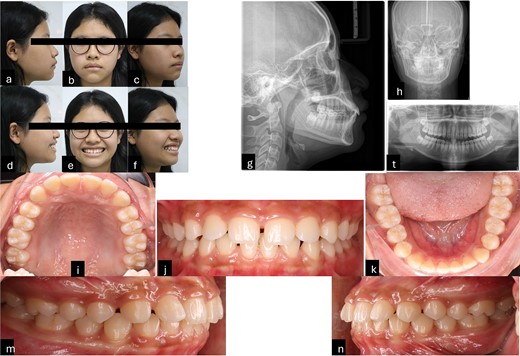

Intraorally, the patient is skeletal Class II with Class I molar, deep curve spee, anterior spacing upper and lower, abnormal position of the tongue and tongue posture, and short teeth were also noted. Extraorally, the patient had convex profile, proclined the upper incisors and GS but the upper lip of the patient was asymmetrical during smiling. The pre-treatment radiographies showed proclined upper incisors, deep curve spee, spacing, and four impacted wisdom teeth (Fig. 1).

Pre-treatment records. (a–f) Extra oral pictures; (g–t) pre-treatment radiographies; (l–n) intraoral pictures.

The patient’s smile revealed 5 mm of gums with clinical manifestations of short and square tooth crowns. The ratio between the length and width of the tooth crown clinically was smaller than on the radiographies. Based on cone beam computed tomography, the alveolar crest of the maxillary anterior teeth was determined to be ~1 mm away from the cementoenamel junction (CEJ). However, a direct assessment of the relationship between the alveolar crest and CEJ using the flap method would be more accurate than surveying on radiographies. Based on the evidence, it was determined that the patient had a GS due to passive teething type 1a, which the osseous crest levels were found to be ~1.5 to 2 mm from the CEJ [4] and hyper mobile lip [5]. In addition, the patient has deep bite with an overbite of 4 mm, the occlusal plane difference between anterior and posterior. Therefore, the cause of a GS is a combination of altered passive eruption and overeruption of the maxillary incisors.